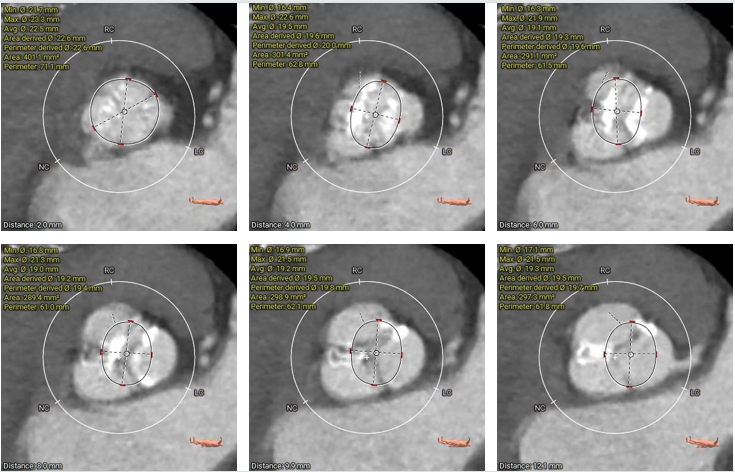

主动脉根部测量

瓣上结构测量